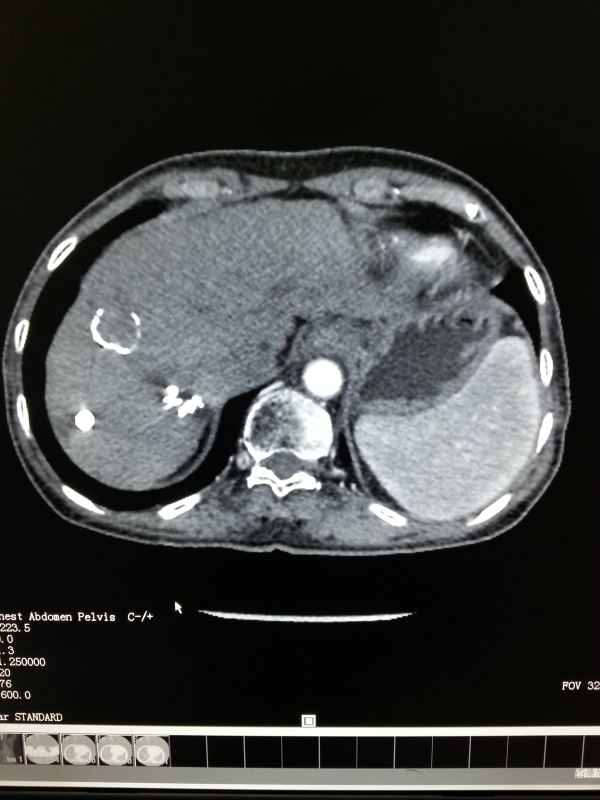

2003年的一天,携带乙肝病毒20余年的李阿姨由于上腹部不适10余天而入住我院肝病内科。入院检查发现肝功能A级,肝脏CT显示肝前叶巨块型肝癌,肿瘤大小为6.0×6.8×6.0cm,包膜完整,但未见癌栓形成。若不采取积极治疗,李阿姨的生存期约只有6个月左右,且随着病情的发展,生存期将会倒计时……。

李阿姨在我院经过“三联疗法”治疗后,再结合长期使用中草药辨证治疗,较好地控制了肝癌的发展。经多次复查肝CT、磁共振等提示肝内病灶稳定并逐渐缩小2-3厘米。至今,她带瘤生存了12年,目前李阿姨像正常人一样生活。

肝癌李秀英2012.6CT右叶肿瘤2厘米,下两个分别为0.5厘米